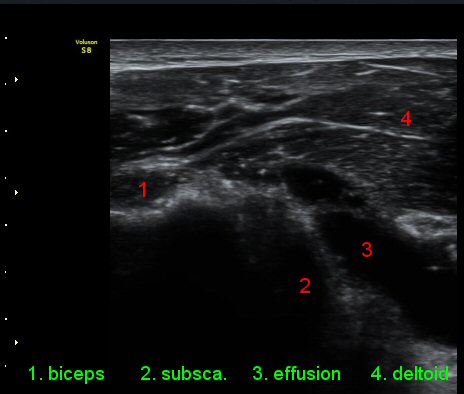

ŽÃÊÀÚ¸¦ ¾à°£ ´Ù¸®ÂÊ, ³»ÃøÀ¸·Î À̵¿ÇÏ´Ï °ß°©ÇÏ±Ù°Ç Ç¥Ãþ¿¡ ¸¹Àº ¾çÀÇ ¼ö¾×Àú·ù°¡ °üÂûµÈ´Ù(»çÁø 3).

ÆÈÀ» ¿ÜȸÀüÇÏ´Ï °ß°©ÇÏ±Ù°Ç Ç¥ÃþÀÇ ¼ö¾×Àú·ù°¡ ´õ¿í È®½ÇÇÏ°Ô °üÂûµµ´Ï´Ù(»çÁø 4).